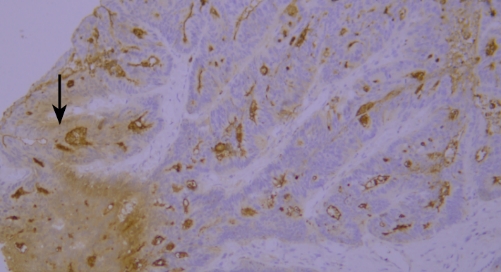

Typical Example:CD34 staining of paraffin-embedded human placental tissue sections:

HRP-directly labeled secondary antibody: Weak positive staining with low background;

Polymer enzyme-labeled secondary antibody: Strong positive staining with clean background and distinct contrast.

Conclusion: Different chromogenic systems yield distinct chromogenic results. Polymer enzyme-labeled secondary antibodies demonstrate higher sensitivity, cleaner background, and more distinct contrast compared to conventional HRP-directly labeled secondary antibodies.